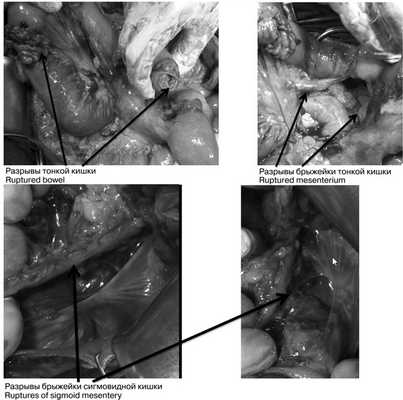

При динамическом наблюдении отмечено нарастание явлений геморрагического шока. С учетом клинико-инструментальной картины заболевания закрытой травмы живота с повреждением внутренних органов и продолжающимся внутрибрюшным кровотечением в экстренном порядке выполнена лапаротомия. Во время доступа в брюшную полость выявлено, что кожа и подкожная клетчатка полностью отсепарированы от подлежащего слоя прямых и косых мышц, имбибированных кровью из-за размозжения (межмышечная гематома) на всем протяжении доступа. Множественные более мелкие гематомы в подкожной клетчатке. В брюшной полости во всех отделах большое количество крови и сгустков (1800 мл), кровь аспирирована с помощью аппарата CellSaver. Продолжающегося активного кровотечения не выявлено. При ревизии органов брюшной полости: в проекции V—VI сегментов правой доли печени по краю выявлена подкапсульная гематома размером около 6×2 см, не пульсирующая, в объеме за время операции не увеличилась. Других повреждений печени по диафрагмальной и висцеральной поверхностям не установлено; на расстоянии 30, 40 и 45 см от связки Трейца 3 разрыва стенки тощей кишки с вскрытием просвета и 1 десерозированный участок. В области разрывов кишки также отмечены участки повреждения брыжейки тонкой кишки (рис. 3), Рис. 3. Разрывы петель тонкой и толстой кишки (интраоперационные фотографии). откуда продолжалось кровотечение. На расстоянии 60 см от связки Трейца выявлен полный поперечный разрыв тощей кишки с разрывом брыжейки кишки до уровня ее корня и активно продолжающимся кровотечением из сосудов брыжейки. Гематома в области брыжейки поперечной ободочной кишки, просвет кишки не вскрыт, гематома в размерах не увеличивается. Помимо этого гематома околокишечной клетчатки вдоль нисходящей ободочной кишки и сигмовидной кишки, брыжейка которой на уровне дистальной трети разорвана; сама сигмовидная кишка в области разрыва брыжейки не изменена, спастически сокращена, просвет не вскрыт, серозная оболочка обычной окраски с небольшими петехиальными кровоизлияниями из-за травмы. Обширная забрюшинная гематома по левому латеральному каналу с распространением на парааортальное клетчаточное пространство и корень брыжейки тонкой кишки. Париетальная брюшина в области левого латерального канала также разорвана, визуализирован левый мочеточник, без повреждений (моча концентрированная, макрогематурии нет). В области боковой стенки живота со стороны париетальной брюшины разрыв стенки размером около 10×5 см с повреждением прямых и косых мышц живота и продолжающимся низкоинтенсивным кровотечением из мышечных сосудов.